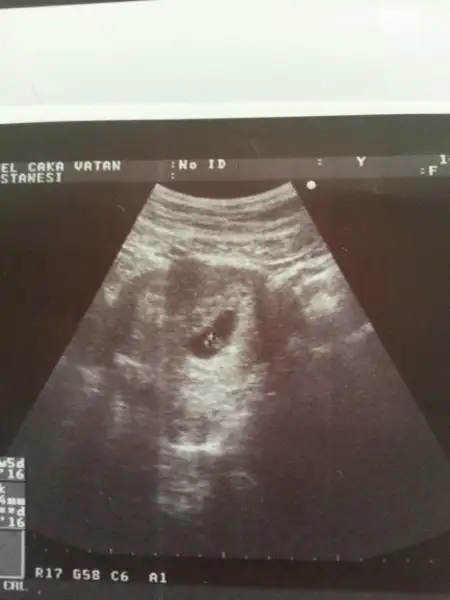

Eki Görüntüle 1707425 Eki Görüntüle 1707427 birde benim miniğime bakarmısınız hanımlar bu 7+4 günlük ultrason görüntüsü

vayyy terbiyesiz, öyle oyunlar yapmayı da öğrenmiş yani şimdiden, çok işim var benim diyosunuz :)Cnm senin bebek bizimle oynuyor:)ilk resimde solda ikinci resimde sağda o yüZden yorum yapmayacağım.sen 11 12 haftalık fotosunu atarsin ilerde o zaman nubuna bakarım.

Benim tahminim eğer karından bakıldıysa bu bebek kızEki Görüntüle 1707425 Eki Görüntüle 1707427 birde benim miniğime bakarmısınız hanımlar bu 7+4 günlük ultrason görüntüsü